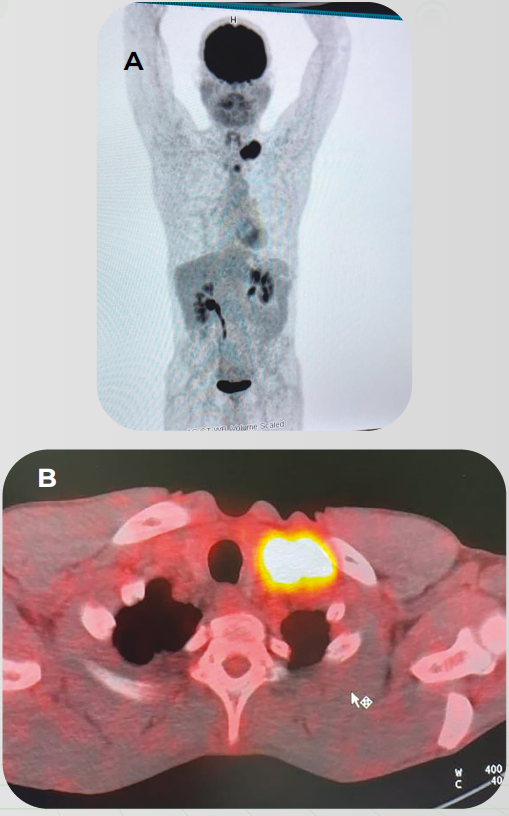

Caso Clínico: Tratamento de paciente com Câncer de Esôfago avançado com PPC>10 em 1L

O caso clínico compartilhado peo oncologista Dr. Rodrigo Guedes, constam detalhes sobre o tratamento de paciente com Câncer de Esôfago avançado com PPC>10 em primeira linha.